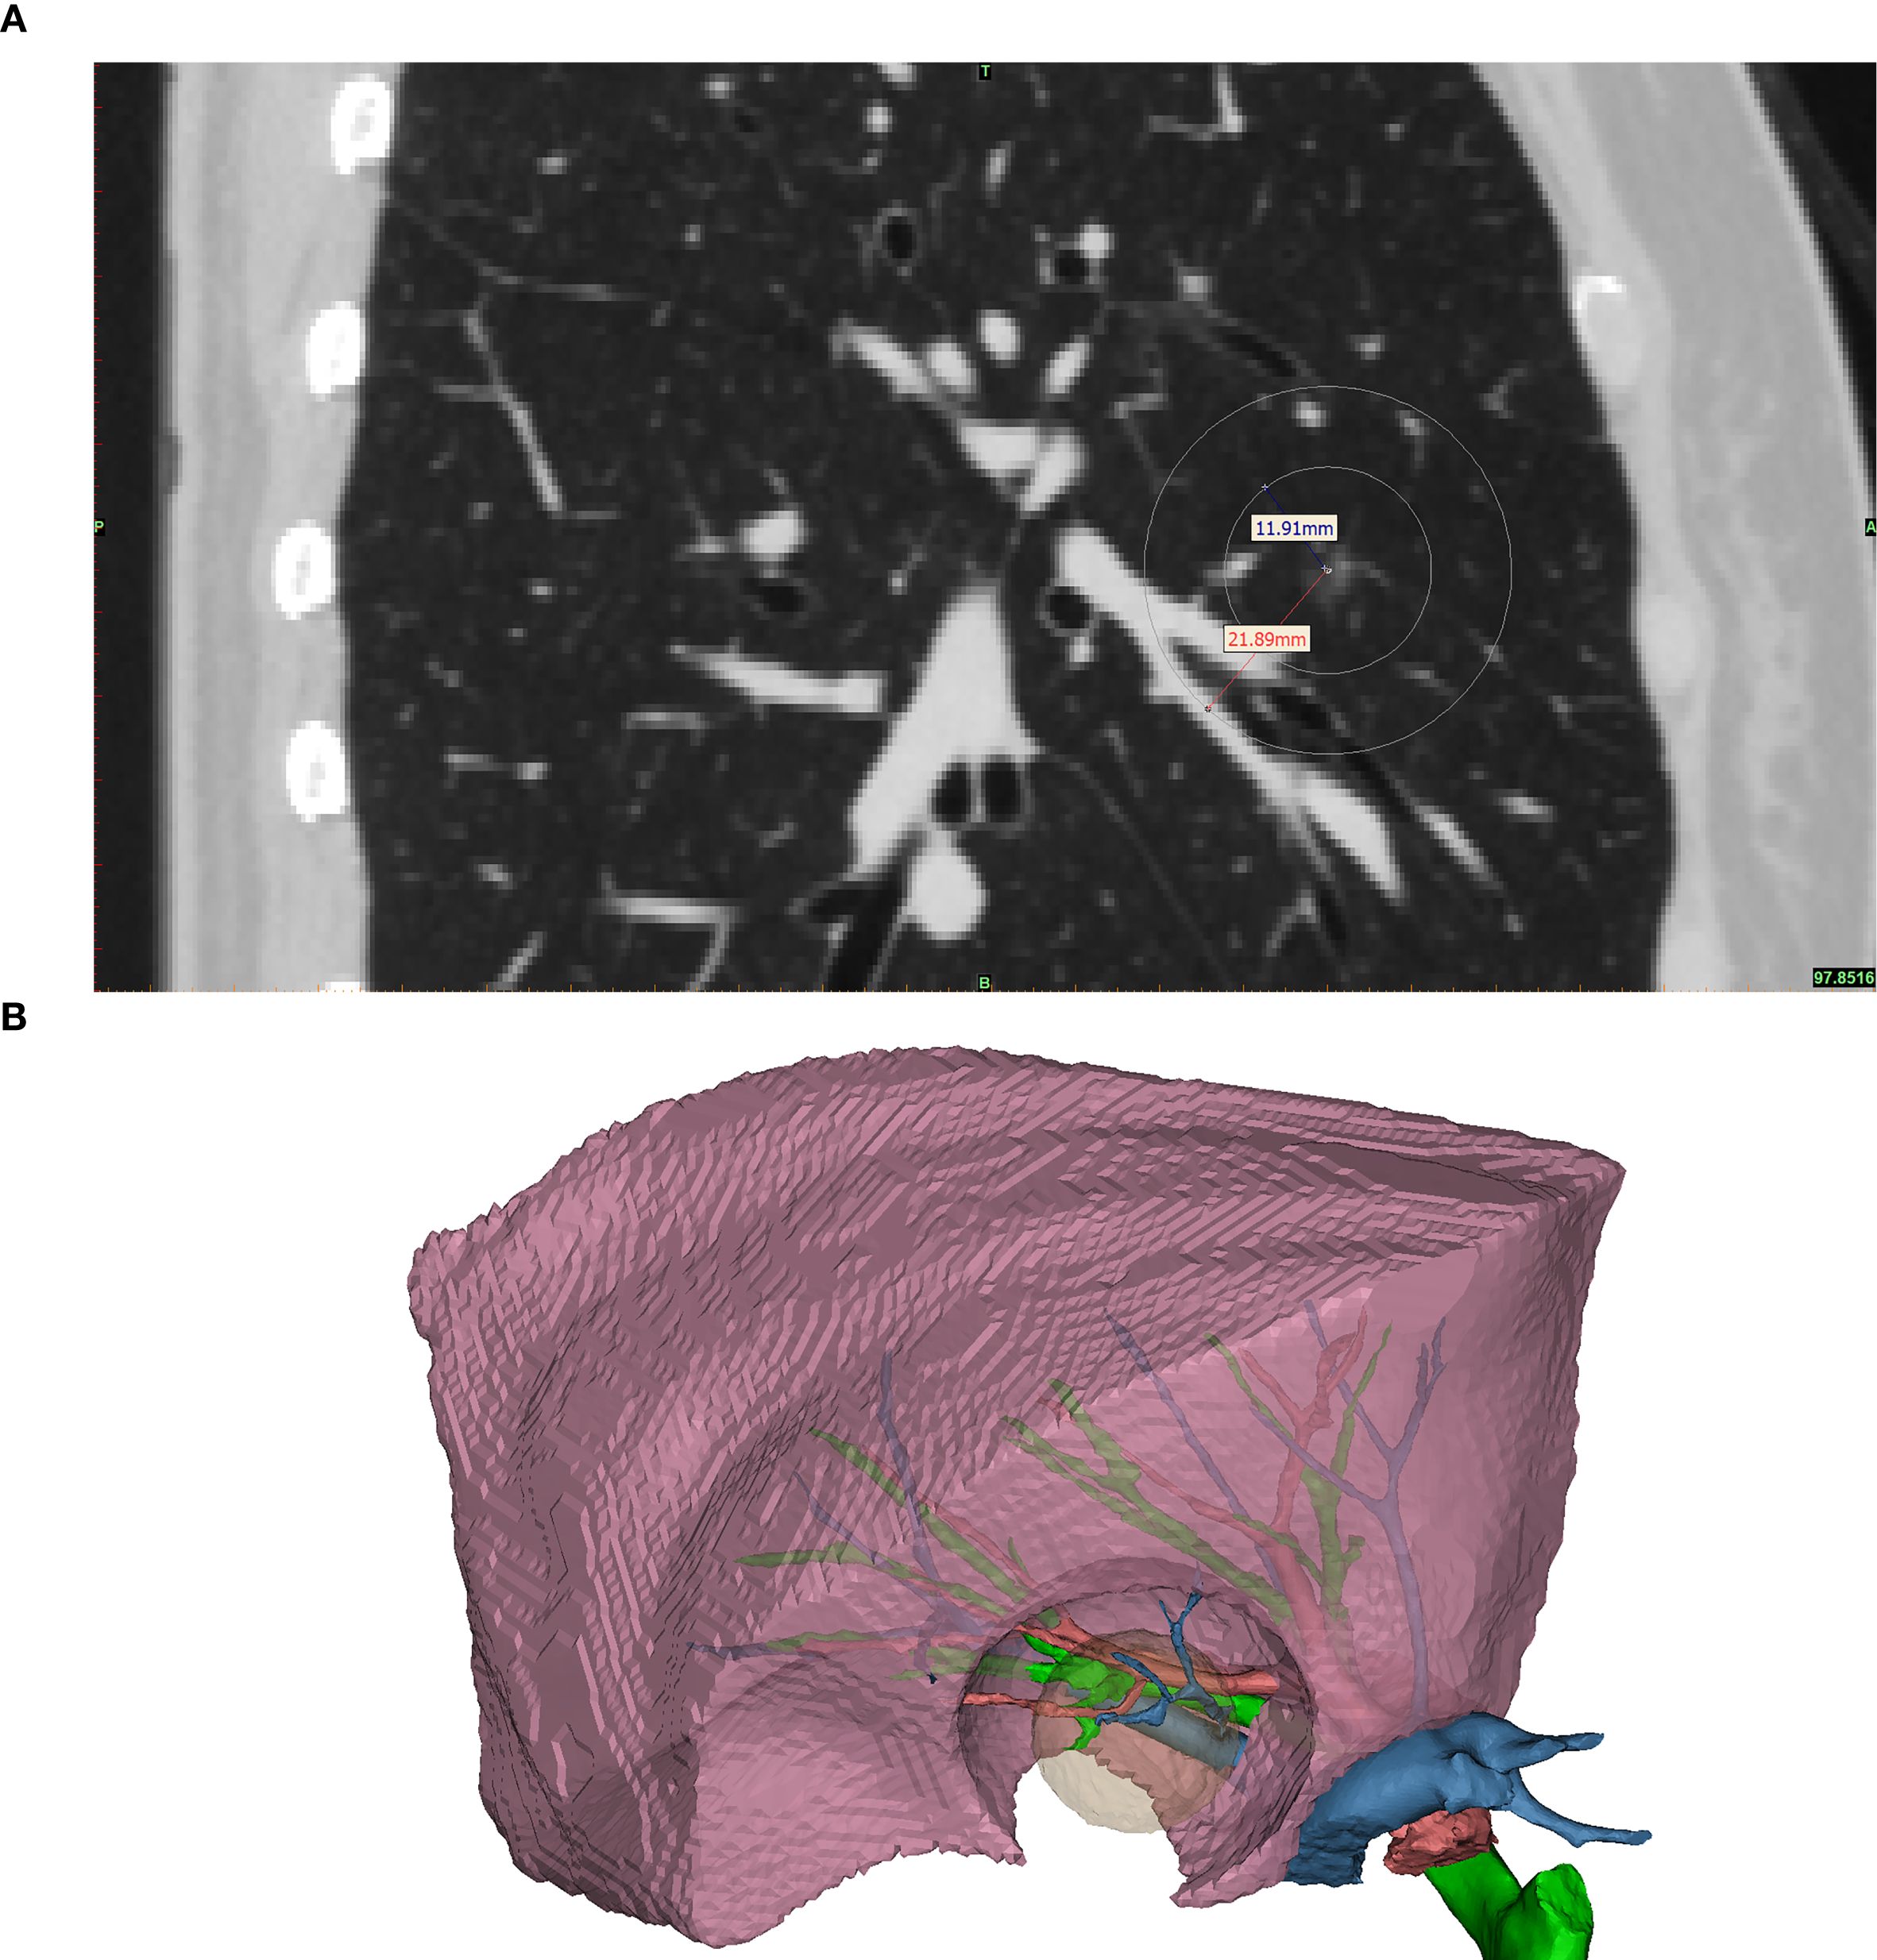

The CONSERVO technique employs a diathermy-based approach to perform wedge resections that conform to the anatomical contour of the lung parenchyma. This technique is designed to minimize unnecessary tissue loss while preserving functional architecture. The major advantage of the diathermy pen, when compared to the staplers, is the millimeter-level accuracy and the ability to shape a non-rigid, thin resectional plane, which is frequently required to preserve adjacent bronchi and pulmonary vasculature (Figure 1A). The required range of resection and the parenchyma that would be affected by the staplers was better illustrated in the 3D reconstructed model (Figure 1B).

Figure 1

Figure 1. The illustrated middle lobe resection range. This figure shows the required resection range and the area of parenchyma that would be affected by the staplers. (A) shows the sagittal plane of the same patient’s preoperative CT scan. The nodule was located at the center of the concentric circles; the inner circle marked the required range of a satisfactory resection, and the outer circle marked the parenchyma that would be affected by the 10mm width staplers. Noted that for this patient, a right middle lobectomy was warranted if stapler-based resection was to be applied, as the stapler would inevitably affect the major bronchi, pulmonary arteries, and veins of the middle lobe. (B) 3D reconstructed model of the middle lobe. The pink object is the reconstructed right middle lobe. The green, red, and blue branching objects are the reconstructed bronchus, pulmonary artery, and vein, respectively. The translucent yellow object is the required resection range, and the hole-like contour in the right middle lobe is the parenchyma that would be affected by the staplers. Noted that a resection by staplers would affect the key structures of the right middle lobe, causing a significant amount of loss of healthy parenchyma.